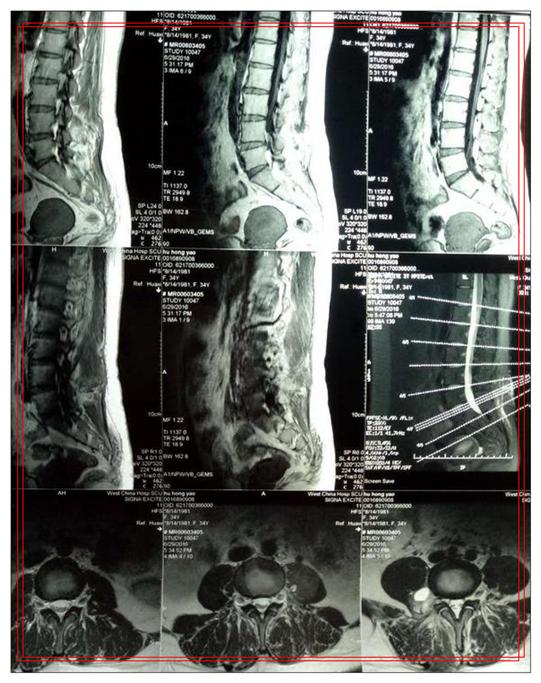

按解剖层次,椎管内肿瘤可分为硬脊膜外、硬脊膜下、硬脊膜髓内肿瘤,其中海绵状血管瘤为较为多见的髓内肿瘤占脊髓血管性疾病的5%~12%。

海绵状血管瘤也称为海绵状血管畸形,是由菲薄缺乏弹性蛋白或平滑肌的血管壁呈分隔状的血管组成在薄壁管道内衬以内皮细胞因而易有出血。椎管内海绵状血管瘤属于隐匿性脊髓血管畸形,是指脊柱的某一节段出现海绵状血管瘤,其危害主要是对脊髓和(或)神经造成影响。

椎管内海绵状血管瘤病例中10%~15%可累及椎弓根,病例以胸椎多见,占60%。临床上,椎管内海绵状血管瘤病例大部分无症状,仅有少部分病例当其椎体病变向硬膜外进展时,可出现临床症状。多数为偶然发现。